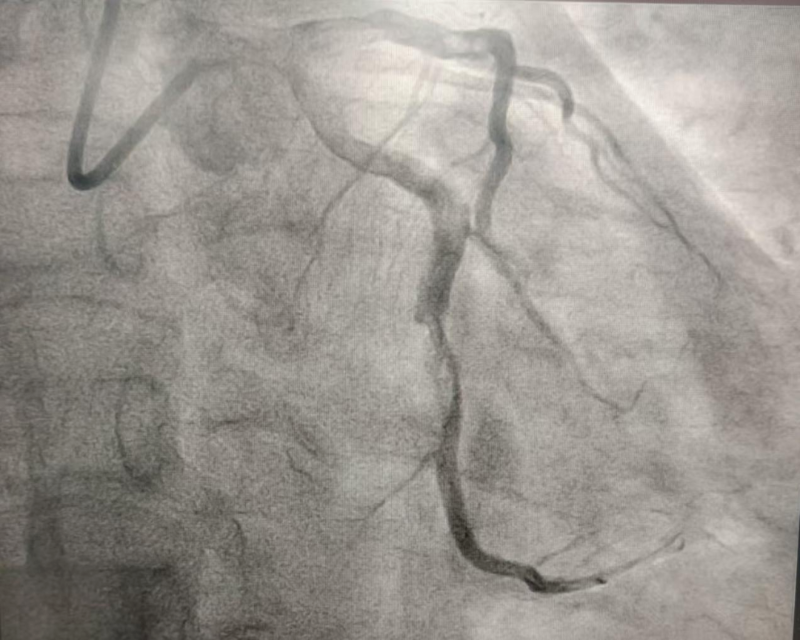

2024年10月的某天,患者程某某因胸悶兩天,前來惠州市中心人民醫(yī)院博羅分院(博羅縣人民醫(yī)院)心血管內(nèi)科就診。經(jīng)診查,診斷為冠心病、急性非ST段抬高型心肌梗死 KillipI級,GRACE評分122分,危險分層高危。行冠脈造影示回旋支遠段近端見大量血栓影、狹窄90%,遠段遠端見大量血栓影、狹窄100%閉塞,前向血流TIMI0級(圖1)。心血管內(nèi)科團隊予為患者行PTCA和血栓抽吸術,復查造影顯示:回旋支遠段近端血栓無變化,遠段遠端血栓消失(圖2)。考慮血栓負荷重,回旋支遠段近端暫不宜行支架置入術,擬給予抗栓治療后擇期復查冠脈造影。

文章配圖

(圖1)